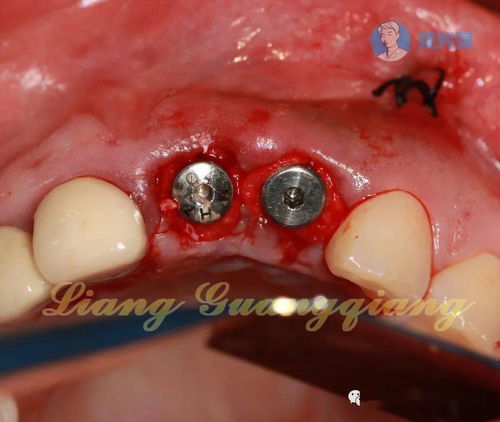

為此種植牙植骨的注意事項有哪些呢?深圳博愛(ài)口腔醫院的專(zhuān)家做了以下相關(guān)的介紹: 種植牙好比種樹(shù)與蓋樓,想種樹(shù),想蓋樓,都必須要有土,而且是質(zhì)量不錯的土,種植牙手術(shù)也是一樣,需要足夠的骨頭。牙齒缺失后,牙槽骨就開(kāi)始了一種不可逆的吸收萎縮,等到想做種植牙的時(shí)候可能就已經(jīng)不夠用了。

這時(shí)候就需要再放上一些骨頭,可能來(lái)自人工材料,可能來(lái)自嘴里其他部位,可能來(lái)自身體的其他部位,要根據不同的情況來(lái)選擇,但總體來(lái)說(shuō)還是一個(gè)常規的可靠的小手術(shù)。 人們意識到種植牙植骨材料應滿(mǎn)足下列要求: 1、種植牙植骨材料必須具有良好的生物相容性 2、種植牙植骨材料可以迅速發(fā)生再血管化,促進(jìn)骨質(zhì)的愈合 3、種植牙植骨材料不影響新生骨與牙種植體之間的骨結合 4、種植牙植骨材料具有骨誘導或骨引導作用 5、種植牙植骨材料的吸收速率與新生骨的成骨速率相協(xié)調,否則植骨材料吸收過(guò)快,將導致成骨不良 6、種植牙植骨材料能恢復缺損區骨質(zhì)的正常形態(tài)與功能。